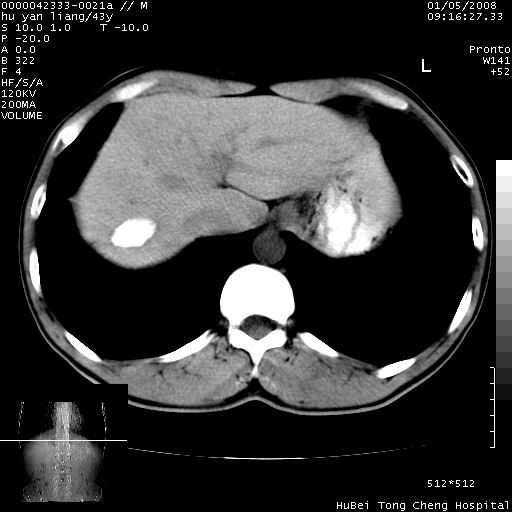

患者 男,43岁。右上腹不适1年余。既往有“肝右叶肝脓肿”病史,经保守治疗后痊愈。

b超提示:1)肝右叶肝内胆管结石。2)肝右叶占位性病变待排。

上中腹部ct轴位平扫+增强扫描(层厚10mm,螺距1.0,重建间隔10mm),图像如下:

肝右上叶偏后方较大团片状钙化灶,支持:肝脓肿后遗改变!

肝右叶后段团块状钙化灶,结合病史考虑肝脓肿痊愈后表现。